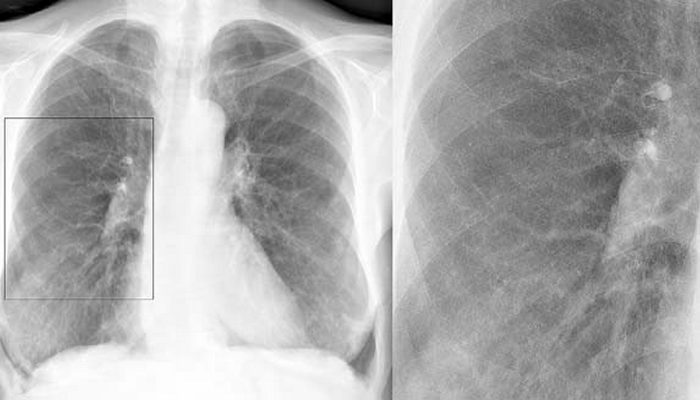

Как отличить бронхит от пневмонии по результатам рентгеновского снимка

классический вариант бронхита на рентген-снимке

пневмония на рентген-снимке: видно почти полное затемнение нижней доли

Несмотря на некоторые различия пневмонии и бронхита, нередко клиника бывает размытой. В такой ситуации для установления верного диагноза необходимо сделать флюорографию или рентгенографию – это наиболее достоверный способ диагностики. По результатам рентгенограммы лечащий врач сможет легко распознать болезнь. Худшие опасения подтвердятся, если на снимке будут отчётливые затемнения.

| Рентген | Усиление лёгочного рисунка | Очаговые затемнения |